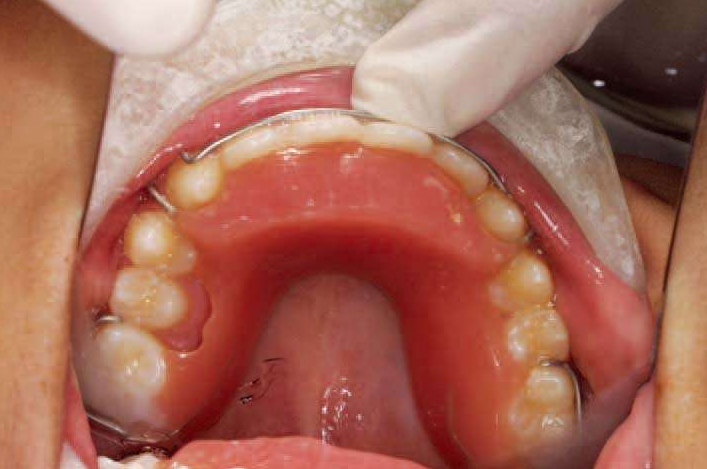

图2 单端悬臂式缺隙保持器

(2)上颌Nance托,下颌舌弓

除了对恒牙萌出有影响之外,当乳牙Ⅳ、Ⅴ早失时恒牙6很容易近中前移,造成牙弓内间隙丢失,临床上很多的牙齿拥挤都是这个原因。

这时候,上颌Nance托,下颌舌弓是比较好的牙弓间隙保持的方法。